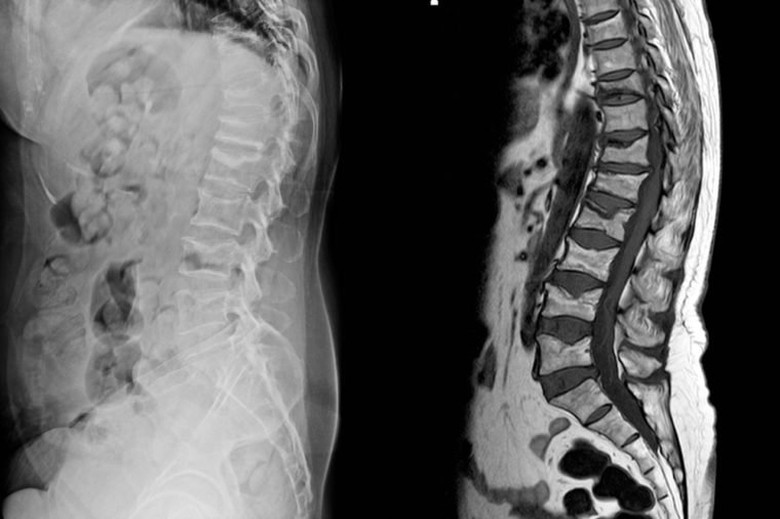

Nếu lưng bị tổn thương do tai nạn giao thông hoặc do va đập, bạn cần được kiểm tra y tế một cách toàn diện. Rất có thể bạn đã bị chấn thương cột sống hoặc một vấn đề nghiêm trọng nào đó. Chụp X-quang hoặc CT là những biện pháp kiểm tra giúp bác sĩ chẩn đoán chính xác tình trạng bạn đang gặp phải.

8. Cảm giác tê

Tổn thương tủy sống có thể dẫn đến tê liệt vĩnh viễn. Nếu bạn bị đau lưng và thường xuyên bị tê vùng chân, hãy đến bệnh viện để được kiểm tra. Nguyên nhân gây ra tình trạng này thường do chấn thương của một hoặc nhiều dây thần kinh vùng thắt lưng. Chấn thương các dây thần kinh có thể gây tê liệt hoàn toàn nếu chúng không được chăm sóc kịp thời.